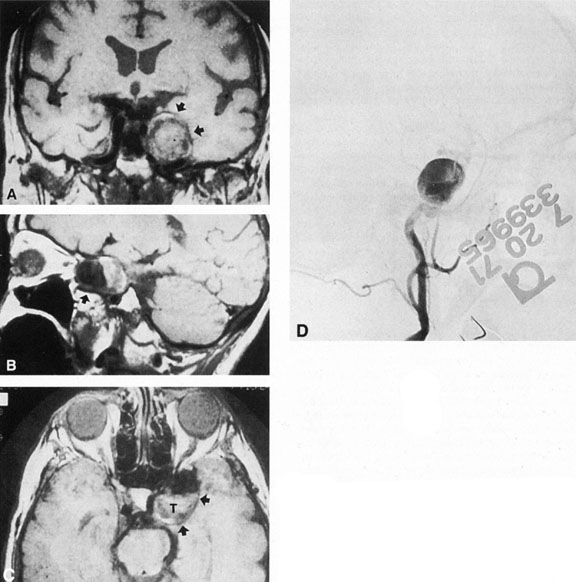

Intracavernous carotid aneurysms constitute only 2% to 3% of all intracranial aneurysms and are unique because of their location. These aneurysms arise from the internal carotid artery as it traverses the cavernous sinus4 (Fig. 3) and therefore produce a specific constellation of ocular and neurologic signs and symptoms. Rupture of such aneurysms, which are almost always saccular, may possibly result in carotid–cavernous sinus fistula, but subarachnoid hemorrhage is rare.5 However, slowly progressive enlargement is the rule, usually occurring within the cavernous sinus, with compression of the third, fourth, and sixth cranial nerves and later involving the first and second divisions of the fifth nerve (see Chapter 12).6 Progressive enlargement of the aneurysm forms a mass in the floor of the middle cranial fossa, compromising motor as well as sensory functions of the trigeminal nerve. Anterior expansion of the aneurysm erodes the anterior clinoid, optic foramen, and superior orbital fissure, eventually producing unilateral visual loss and exophthalmos. Posterior expansion, which occurs later, can erode the petrous portion of the temporal bone, causing ipsilateral facial palsy and, rarely, deafness. The sphenoidal sinus and the nasopharynx may infrequently be involved by inferior expansion and medial extension erodes into the sella and may simulate a pituitary tumor7 or cause bilateral ophthalmoplegia.8 Bilateral saccular intracavernous aneurysms occur uncommonly.9

Fig. 3. Magnetic resonance images of intracavernous aneurysm in a 72-year-old woman with left retrobulbar pain and sixth-nerve palsy. A: Coronal section (TR, 800 ms; TE, 30 ms). B: Parasagittal section (TR, 1000 ms; TE, 20 ms). C: Axial section (TR, 800 ms; TE, 30 ms). Note partial occlusion by thrombus (T). D: In a similar patient, carotid arteriogram (subtracted, lateral view) demonstrates a large intracavernous aneurysm.

The onset of signs and symptoms is usually insidious, at times accompanied by pain about the eye and frontal area on the involved side. The pattern of serial involvement of the cranial nerves within the cavernous sinus is usually as follows: sixth, third, fifth, and fourth. Occasionally, palsies evolve simultaneously and the ipsilateral optic nerve may eventually be encroached on by superior expansion of the aneurysm. The pupil is often not dilated maximally, as in the usual acute third-nerve palsy; it may be relatively small (rarely immobile) because of simultaneous involvement of the oculosympathetic fibers.6 Barr and associates4 believed that such aneurysms usually arise as a weakness in the lateral wall of the carotid artery within the cavernous sinus and that the aneurysm tends to expand laterally between the third and fourth nerves superiorly and the sixth nerve inferiorly, finally compressing the nerves on the medial wall of the aneurysmal sac rather than laterally. Late involvement of the fifth nerve is emphasized by the findings that, in the three studied cases, this nerve was not splayed over the lateral aspect of the aneurysm, but that it lay mainly inferior, lateral, and posterior in the region where late expansion of the aneurysm occurs. Although periocular pain has often been emphasized as a prominent symptom, it may not occur until ophthalmoplegia has been present for years.

Intracavernous aneurysms are suspected by the clinical presentation of a chronic cavernous sinus syndrome and are diagnosed by enhanced computed tomography (CT), magnetic resonance imaging (MRI), and arteriography (see Fig. 3). Because of the location and configuration within the cavernous sinus, direct surgical approaches to cavernous carotid aneurysms are hazardous. In recent years intravascular occlusion of the internal carotid by detachable balloon has evolved as a safe and successful procedure, often with relief of pain and improvement in ophthalmoplegia.10 Unfortunately, these balloons are commercially unavailable at the time of this writing.